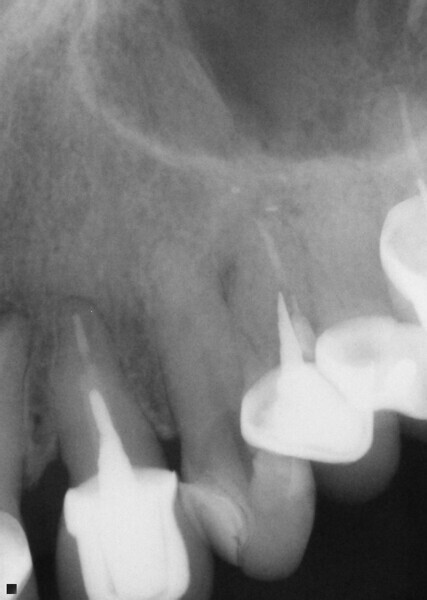

Fig. 14: Patient presented with complaint of pain on chewing on teeth 14 and 15 with increasing sensitivity to hot.

Fig. 15: Instrumentation performed with ExactTaperH DC files and obturation with a single cone of GP and Bioceramic Root Canal sealer completing endodontic treatment.

Fig. 16: Patient presented with percussion and hot sensitivity on the lower first molar that she reported was increasing over the past week.

Fig. 17: Instrumentation was performed with ExactTaperH DC files and single cone obturation with Bioceramic Root Canal sealer completing the endodontic treatment preserving the cervical tooth structure during the treatment.